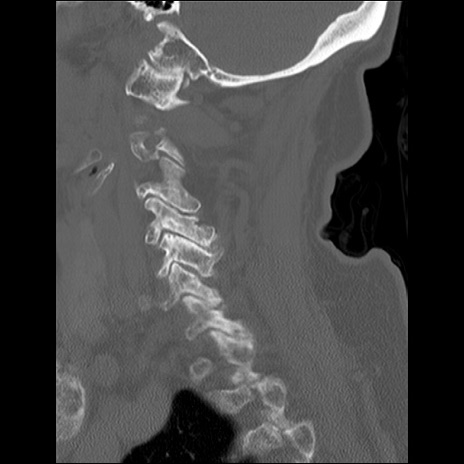

症例48 頚椎CT(矢状断像)

頚椎CT